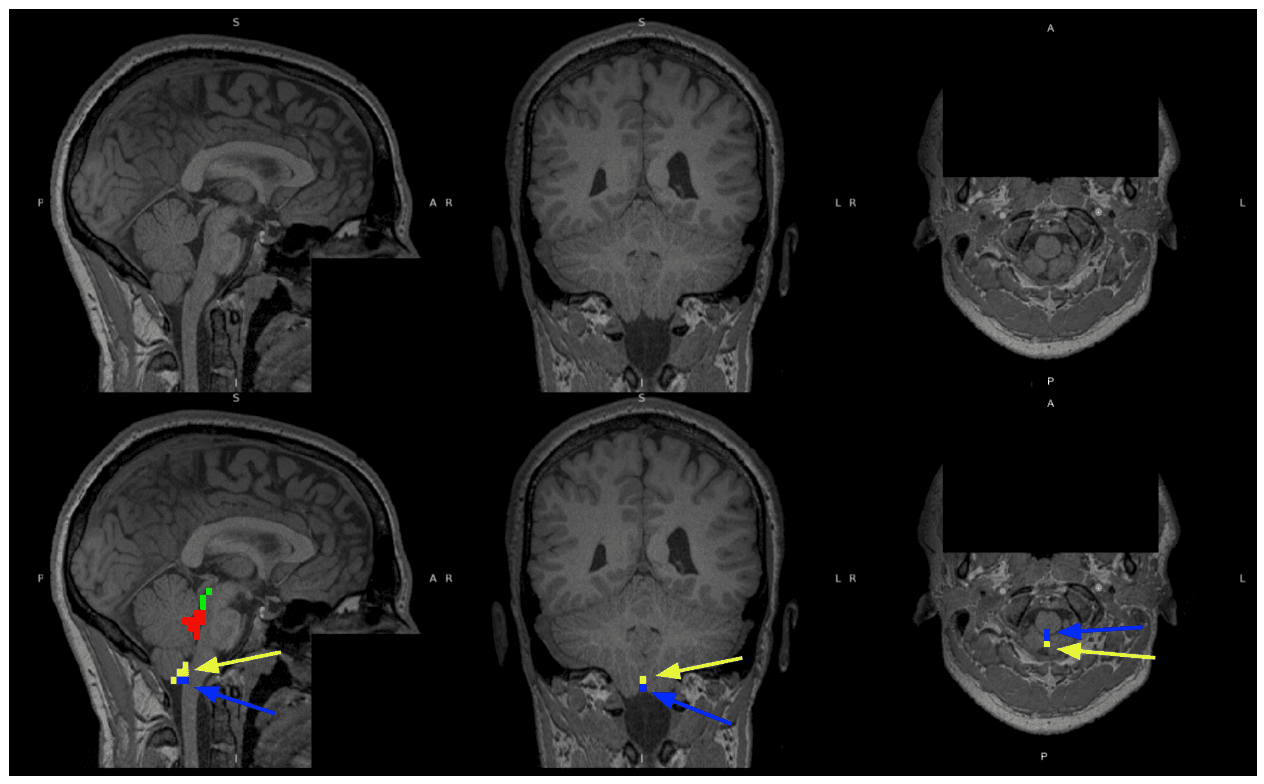

The use of photobiomodulation (PBM) to enhance brain health, specifically glymphatic drainage and thus neurotoxic waste clearance, may make it a promising therapeutic tool against neurodegenerative diseases such as Alzheimer's disease. This study investigates whether PBM can modulate cerebrospinal fluid (CSF) flow in 45 healthy young adults. We conducted forehead transcranial PBM (tPBM) and intranasal PBM (iPBM) at the nostril level, and measured CSF dynamics using blood-oxygenation level-dependent (BOLD) functional MRI (fMRI). Our data demonstrates 4 min of PBM-induced increases in CSF flow. Our data shows that (1) even a short PBM of 4 min can induce a change in CSF dynamics, in the form of an immediate increase in intracranial CSF volume and a reduction in CSF inflow; (2) skin melanin had a significant effect on the CSF response in tPBM, with lighter skin associated with higher responses; (3) both iPBM and tPBM displayed a dose-dependent effect on CSF dynamics in terms of a irradiance-wavelength interaction; (4) intranasal PBM (iPBM) can be used to produce a significant change in CSF dynamics that is equivalent to forehead transcranial PBM (tPBM) with a small fraction of the irradiance. The most likely explanation for the observed fMRI signal changes in CSF regions of interest for both tPBM and iPBM is an increased CSF outflow pressure due to PBM-induced vasodilation that transiently increases intracranial CSF volume and reduces net CSF inflow. This study establishes that PBM can modulate CSF flow in the healthy human brain in real time. This study also suggests that iPBM may be more efficient in CSF modulation due to the proximity to the olfactory system and the lack of melanin dependence. The influence of melanin on tPBM, the feasibility of iPBM and the dose dependence of both will require further investigation in healthy and patient populations.